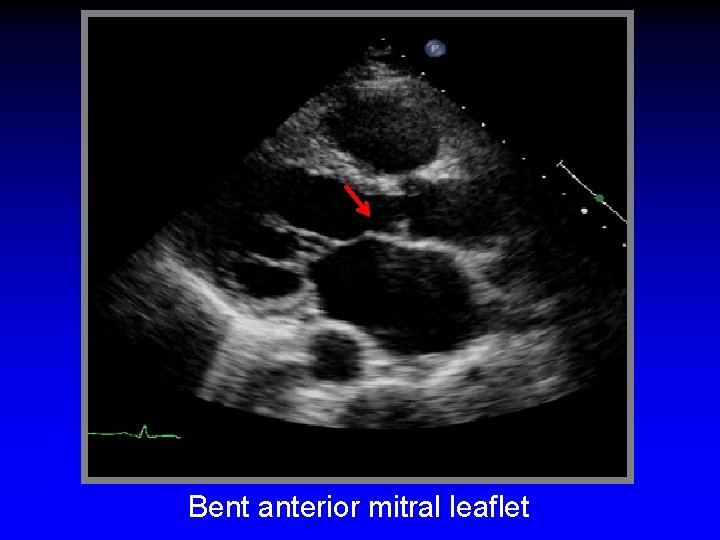

Apical Tethering of Mitral Leaflets Basal cord tents anterior leaflet (“seagull sign”)

Basal cord tents anterior leaflet (“seagull sign”) Increased tenting area

Bent anterior mitral leaflet